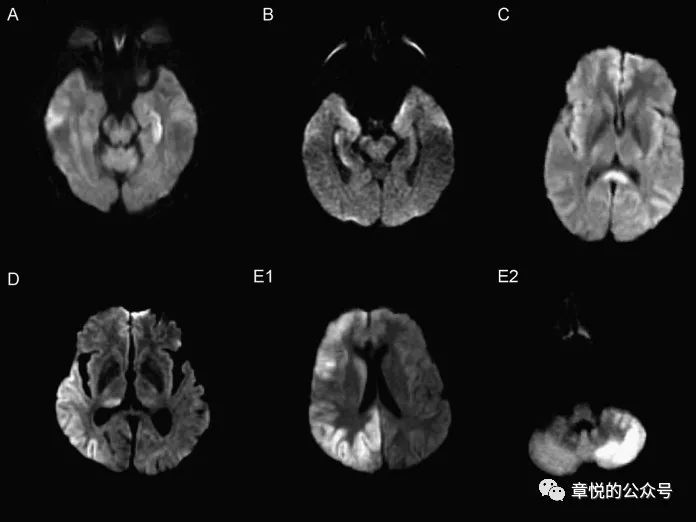

病人入院后癫痫频发,那会不会是癫痫后的表现呢?癫痫持续状态后出现磁共振异常表现的概率为11.6%,主要的改变有海马受累,胼胝体压部受累,皮层加丘脑受累,皮层受累和小脑交叉性失联络等(图8),影像改变能持续多长时间没有大宗报道,从小样本的研究看,部分病例在发病2周时仍旧有信号改变,这一点我们的案例倒是符合的。

图8 癫痫后脑磁共振异常的形态,海马受累,胼胝体压部受累,皮层加丘脑受累,皮层受累和小脑交叉性失联络等。(Milligan TA. et alFrequency and patterns of MRI abnormalities due to status epilepticus. Seizure- European Journal of Epilepsy , Volume 18 , Issue 2 , 104 – 108)